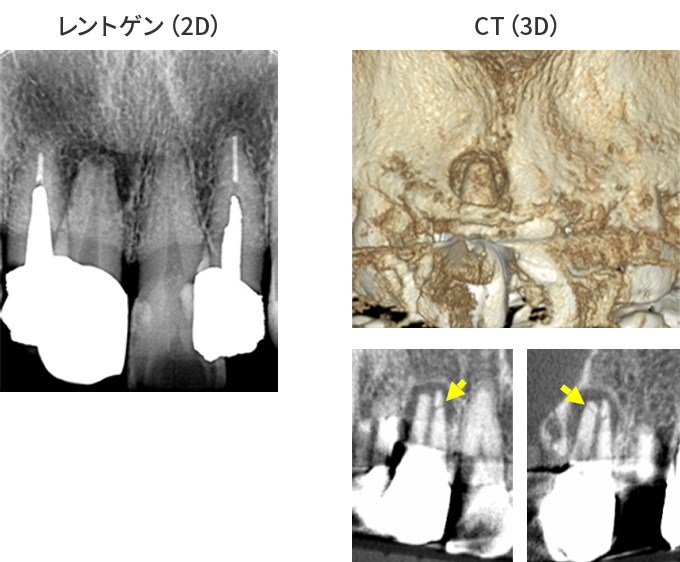

CT撮影で根の状態を“立体的”に診断

レントゲンは2Dですが、CT(3D)では病変の広がり・分岐・湾曲・破折線を正確に把握できます。

特に、

- 他院で治らなかった根尖病変

- 大臼歯の複雑な形態

- 器具破折の有無

- 嚢胞の存在

などはCTでしか判断できません。“診断の精度=治療の成功率” であるため、CT診断は必須です。